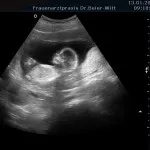

Frühschwangerschaft:

Ultraschall_19